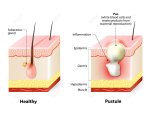

Пиздец, какая микрофлора кишечника, какая кровь нахуй. Анон, ты хотя бы фак читал? Тебя наебали, а ты и сам обманываться рад. Чаще всего прыщи ничего общего не имеют с проблемами кишечника, и «внутренняя проблема» заключается в генетической предрасположенности к неадекватной работе сальных желёз, из-за малейших/рандомных триггеров сальные железы начинают вырабатывать очень много сала, вызывая закупорку пор, тогда внутри кожи начинают размножаться бактерии акне(так и называются Cutibacterium acnes), развивается воспаление, опять же из-за закупорки пор, и мы получаем прыщи и чёрные точки. Всё. Более прошаренные аноны, поправьте, если где-то сказал не так.

Пиздец, какая микрофлора кишечника, какая кровь нахуй. Анон, ты хотя бы фак читал? Тебя наебали, а ты и сам обманываться рад. Чаще всего прыщи ничего общего не имеют с проблемами кишечника, и «внутренняя проблема» заключается в генетической предрасположенности к неадекватной работе сальных желёз, из-за малейших/рандомных триггеров сальные железы начинают вырабатывать очень много сала, вызывая закупорку пор, тогда внутри кожи начинают размножаться бактерии акне(так и называются Cutibacterium acnes), развивается воспаление, опять же из-за закупорки пор, и мы получаем прыщи и чёрные точки. Всё. Более прошаренные аноны, поправьте, если где-то сказал не так.